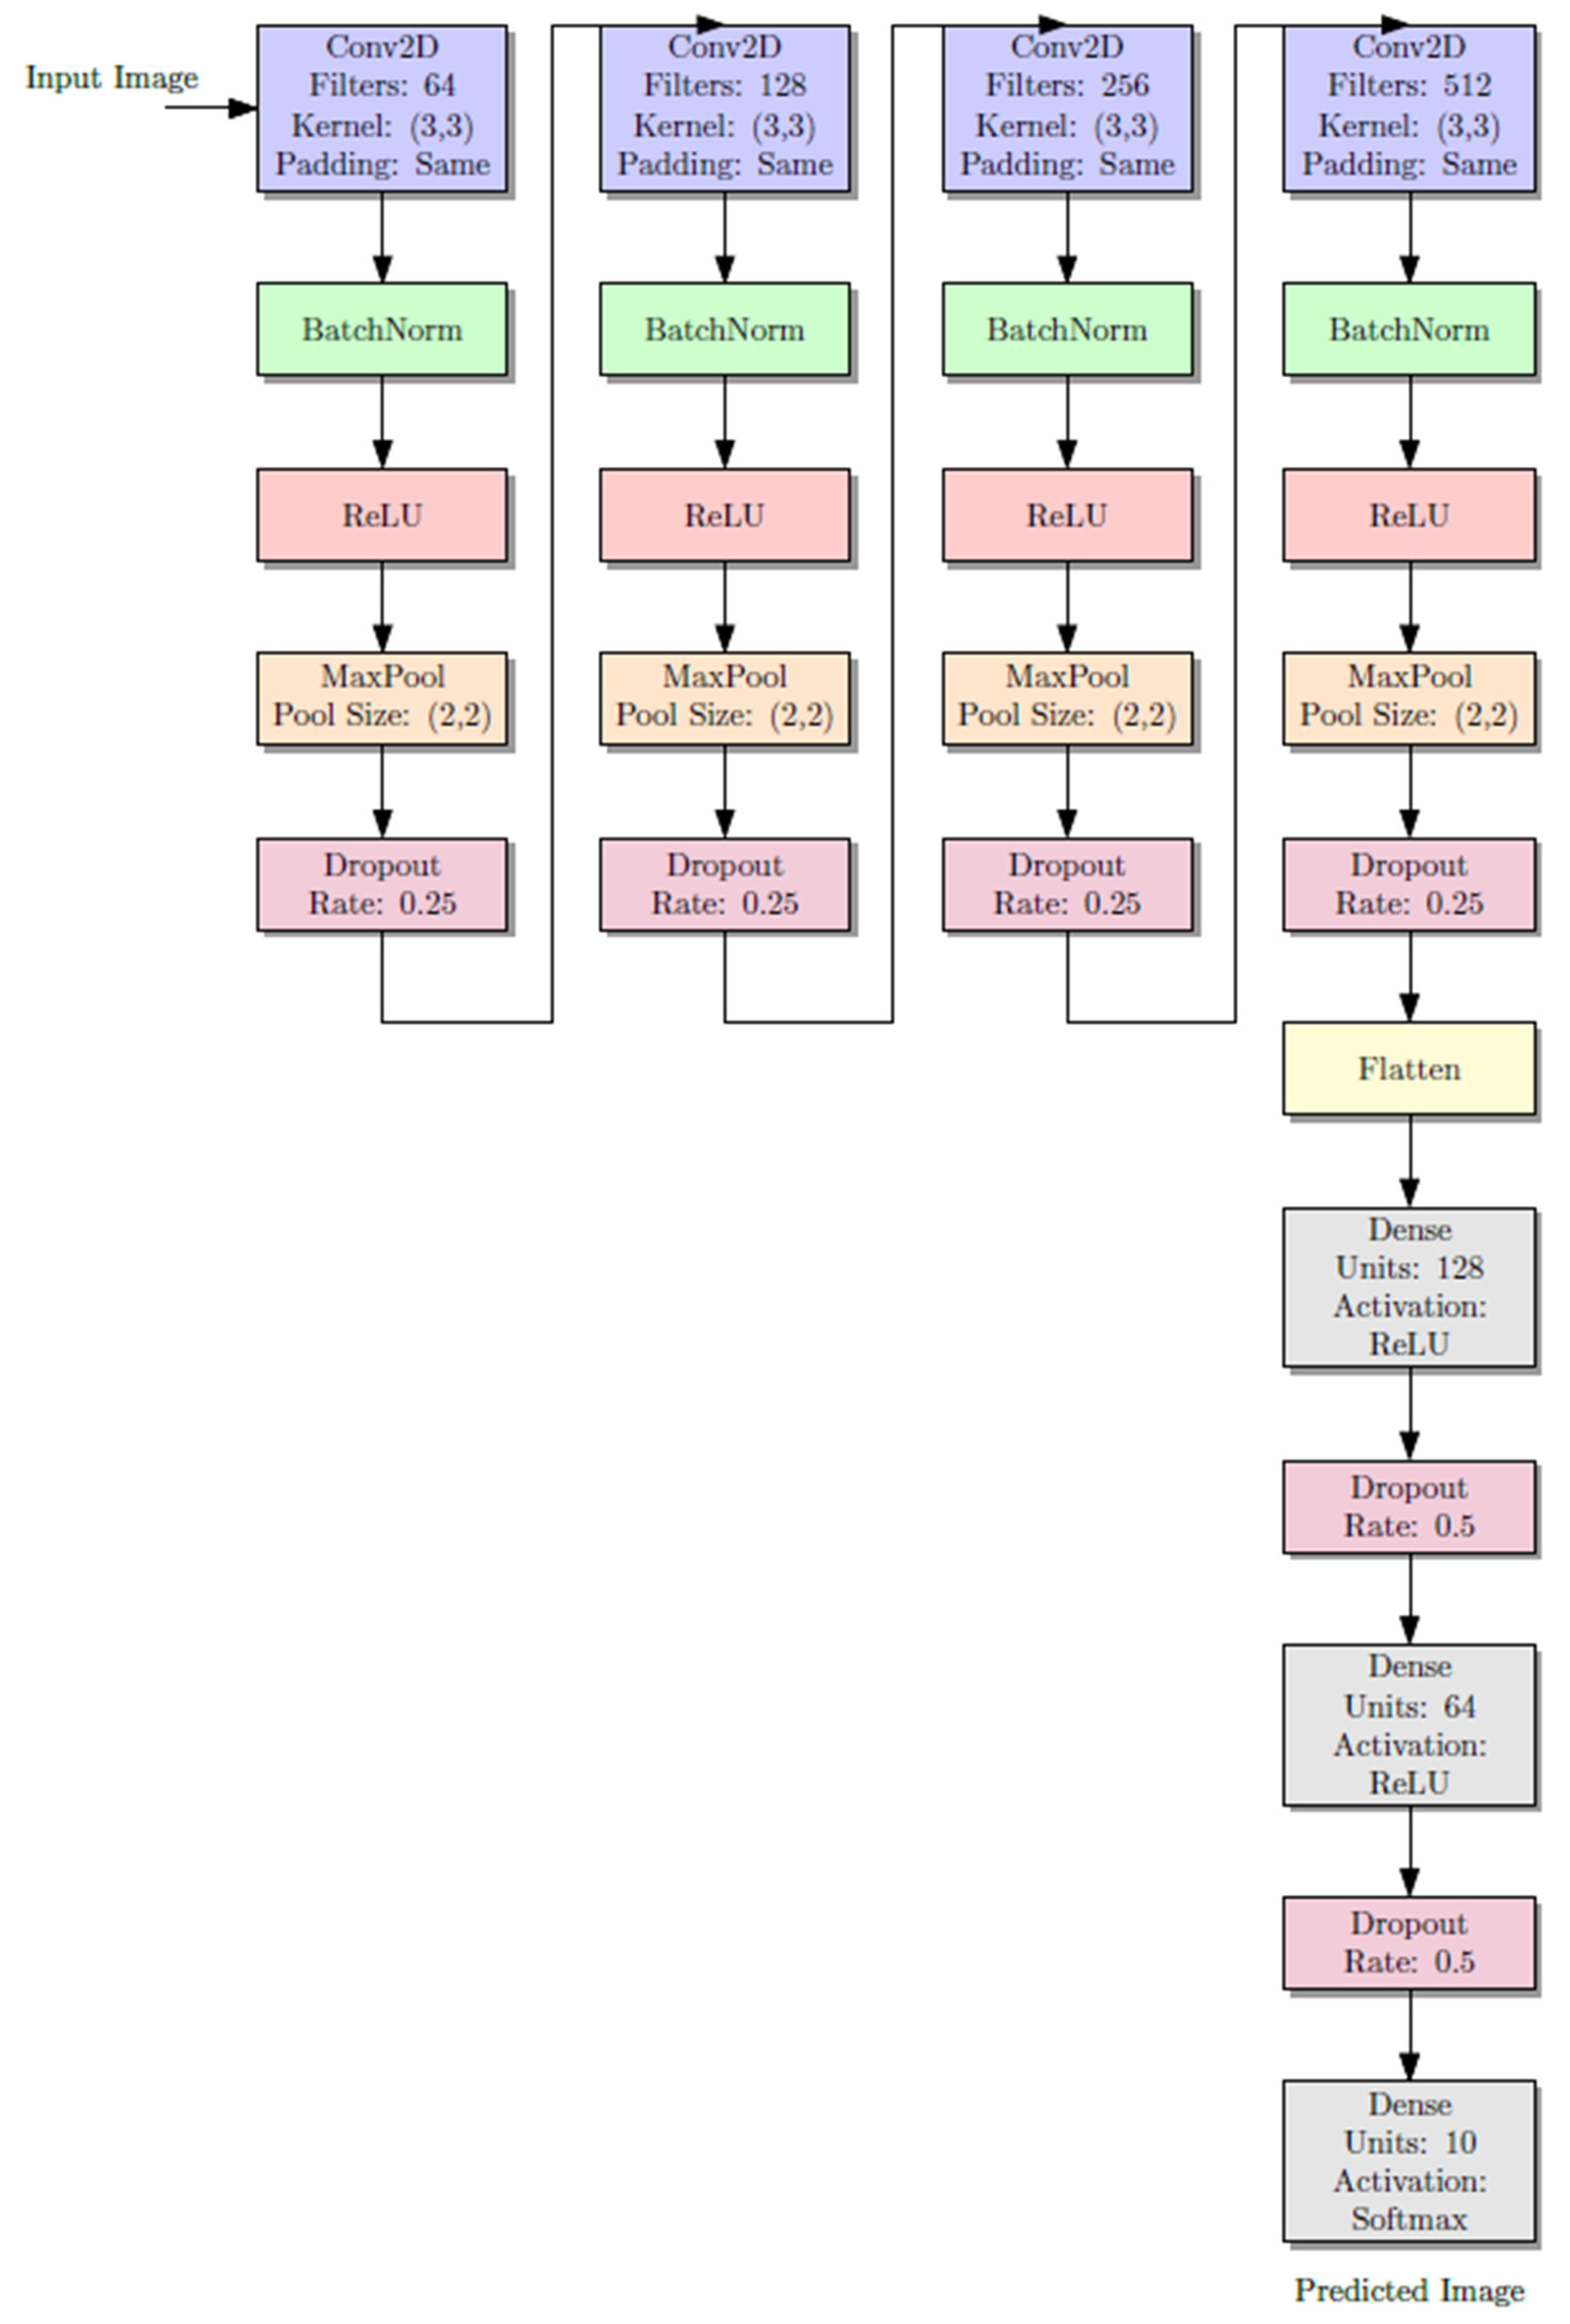

Every CNN is simply three convolutional layers with ReLU activations, followed by max pooling layers to down-sample the features spatially.

16]. By employing three convolutional layers, our study ensures sufficient complexity to capture the morphological variations in calcification stages while remaining computationally efficient and clinically practical for integration into real-world diagnostic workflows. Beside ReLU activation function was applied after each of the three convolutional layers that comprised the CNN architecture. Given the size of the dataset, this configuration was selected to preserve a balance between representational power and overfitting risk. Due to its demonstrated ability to accelerate training and mitigate vanishing gradient problems, ReLU was selected. Preliminary experiments tested deeper architectures, but they frequently resulted in overfitting and did not produce appreciable accuracy gains. This design aligns with several earlier studies in medical imaging and dentistry, where moderately deep CNNs (3 to 4 layers) have demonstrated generalization while achieving high classification accuracy.

In order to combat overfitting, dropout layers (rate 0.5) were used. The last output layer was a fully connected dense layer with a SoftMax activation function for multi-class classification. The SoftMax equation is shown as follows.

Figure 3 illustrates the diagram of the CNN architecture model, which displays the activation functions of the layers and the output layers. Each model consists of three convolutional layers activated with rectified linear unit (ReLU) functions, followed by max-pooling layers that reduce the spatial dimensions and extract the most relevant features. Dropout layers (rate = 0.5) were incorporated to minimize overfitting by randomly deactivating a subset of neurons during training. The final fully connected dense layer, equipped with a SoftMax activation function, outputs the probability distribution across multiple Demirjian developmental stages (C–H). The diagram highlights the sequential flow of data from input (cropped ROI of the lower second molar or canine) through convolutional feature extraction, pooling, and dropout, to the classification output. This layered structure allows the model to progressively learn hierarchical features of dental calcification patterns and reliably assign developmental stages. The complete model pipeline is shown in

Figure 3. As in any pipeline, the input OPG image goes through a preprocessing step, which includes cropping the image to the relevant regions. In this case, the relevant regions are the areas containing the canines and the molars, henceforth referred to as ROIs. In the subsequent steps, each ROI is processed through the appropriate branch of the CNN; the canine crop goes through the branch dedicated to canine classification and the molar crop goes through the branch for molar classification. The classification of Demirjian stages is carried out in each branch after going through several convolutional and pooling layers in order to extract the relevant features. The model can specialize for the different anatomical features of canines and molars because of the separate pathways.